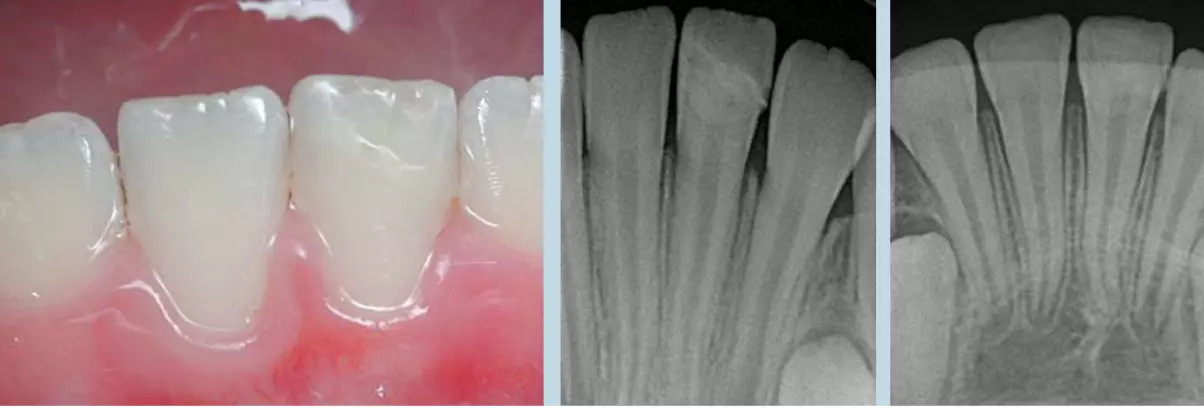

Пример реставрации фрагментом зуба

Пример реставрации фрагментом зуба. Отреставрирован нижний центральный резец слева. Рентген сразу и через 12 месяцев после лечения.

Наблюдение за пациентом после биологического метода лечения травмы зуба осуществляется в течение 12-24 месяцев. Сначала врач приглашает на осмотры ребенка через 1 месяц, затем на 3, 6 и 12 месяцы. При необходимости контрольные осмотры проводятся на 18 и 24 месяц после лечения.

Во время контрольного визита врач делает прицельный рентген-снимок зуба. Травмы часто случаются в зубах, корни которых еще не закончили формирование. Рентгенологическое исследование помогает доктору убедиться – корень зуба в порядке, в пульпе или пространстве за верхушкой корня не возникли воспалительные процессы.